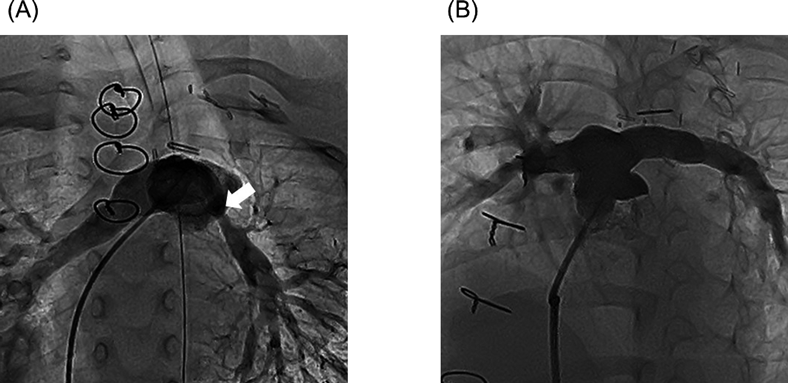

(A) Before the left original Blalock–Taussig shunt: The mediastinal portion of the left PA from the main PA is absent. The ductus arteriosus is diminishing and the arrow indicates a ductal stump at the base of the brachiocephalic artery. The distal left PA is hypoplastic. (B) After the definitive repair (before the balloon angioplasty): The mediastinal portion of the left PA is reconstructed, the arrow indicates the stenotic region. The distal left PA has grown. PA, pulmonary artery.

A 2-month-old female (weight 5.0 kg) with right aortic arch, left IPADO, and patent foramen ovale, was referred to our center for surgical treatment. Her diagnosis was confirmed by enhanced chest computed tomography and cine angiography, which revealed a diminishing ductus arteriosus from the brachiocephalic artery to the distal left PA which was hypoplastic (Fig. 1A). Imaging results raised concerns about a non-negligible difference in diameters and pulmonary vascular resistances between the right and left PAs. This could result in imbalanced PA flow after primary repair leading to non-symmetric PA growth, and, in particular, persistent hypoplasia of the left PA. Thus, we chose a staged approach. When over-shunted either by constructing a modified Blalock–Taussig (BT) shunt or stenting the duct, pneumorrhagia may be the result because of too much flow to the left PA, which may cause. On the other hand, if the initial shunt was too small, repeated construction of a shunt would be required with a short interal, because a 2-month-old baby could grow rapidly. Hence, we chose an original BT shunt, which becomes larger as the patient grows, for the first stage palliation. The original BT shunt was performed on the left side, followed by balloon angioplasty 3 months later.

One month later, the mean PA pressure was 23 mmHg. Balloon angioplasty was performed for mild stenosis of the reconstructed left PA, and the stenotic region was dilated from 2.8 mm to 6.0 mm (Fig. 1B, Fig. 3A). The right-to-left lung perfusion ratio improved during follow-up from 3.63 at 2 months to 2.05 at 19 months after the definitive repair. Mean PA pressure and pulmonary vascular resistance also improved from 23 mmHg and 1.71 U·m2 at 1 month to 16 mmHg and 1.17 U·m2 at 13 months, respectively. The diameters of the bilateral PAs became more symmetrical (Fig. 3B). That of the right PA and the left PA were 7.3 mm and 7.6 mm, respectively. Pressure gradients between the main PA and the bilateral PAs also became equivalent: 9 mmHg for the right PA and 7 mmHg for the left PA at 13 months.